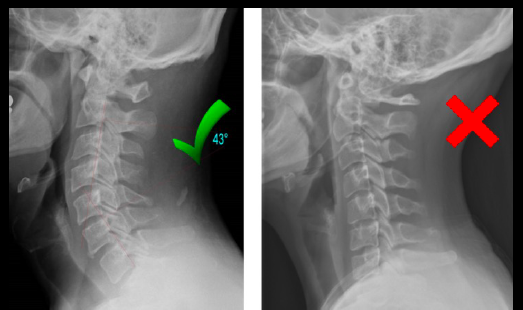

¿Qué se toma en cuenta en la Alineación? (5)

• Huesos largos

• Alineación del propio hueso

• Alineación del hueso con otros

• Curvaturas

• La columna se puede interpretar

como un solo hueso y sus

componentes